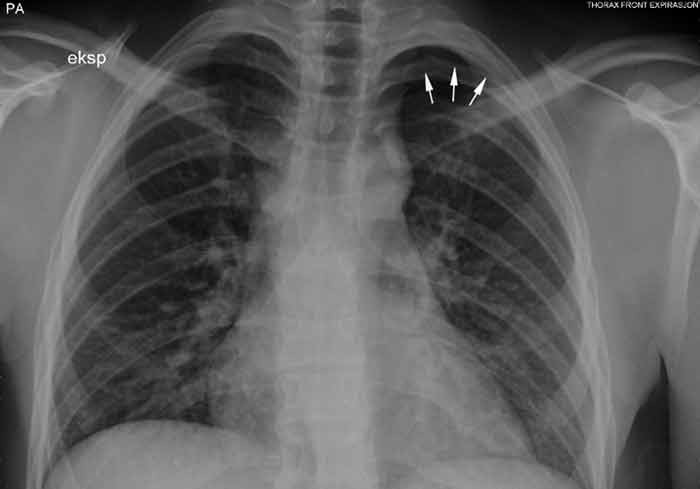

This information led to a renewed review of his stay in our hospital. Close inspection of the X-rays of the lungs showed a small, apical air cap on the left side which measured about 12 mm during expiration (Fig. 1).

Figure 1  Chest X-ray taken during expiration shows a 12 mm apical air cap on the left side.